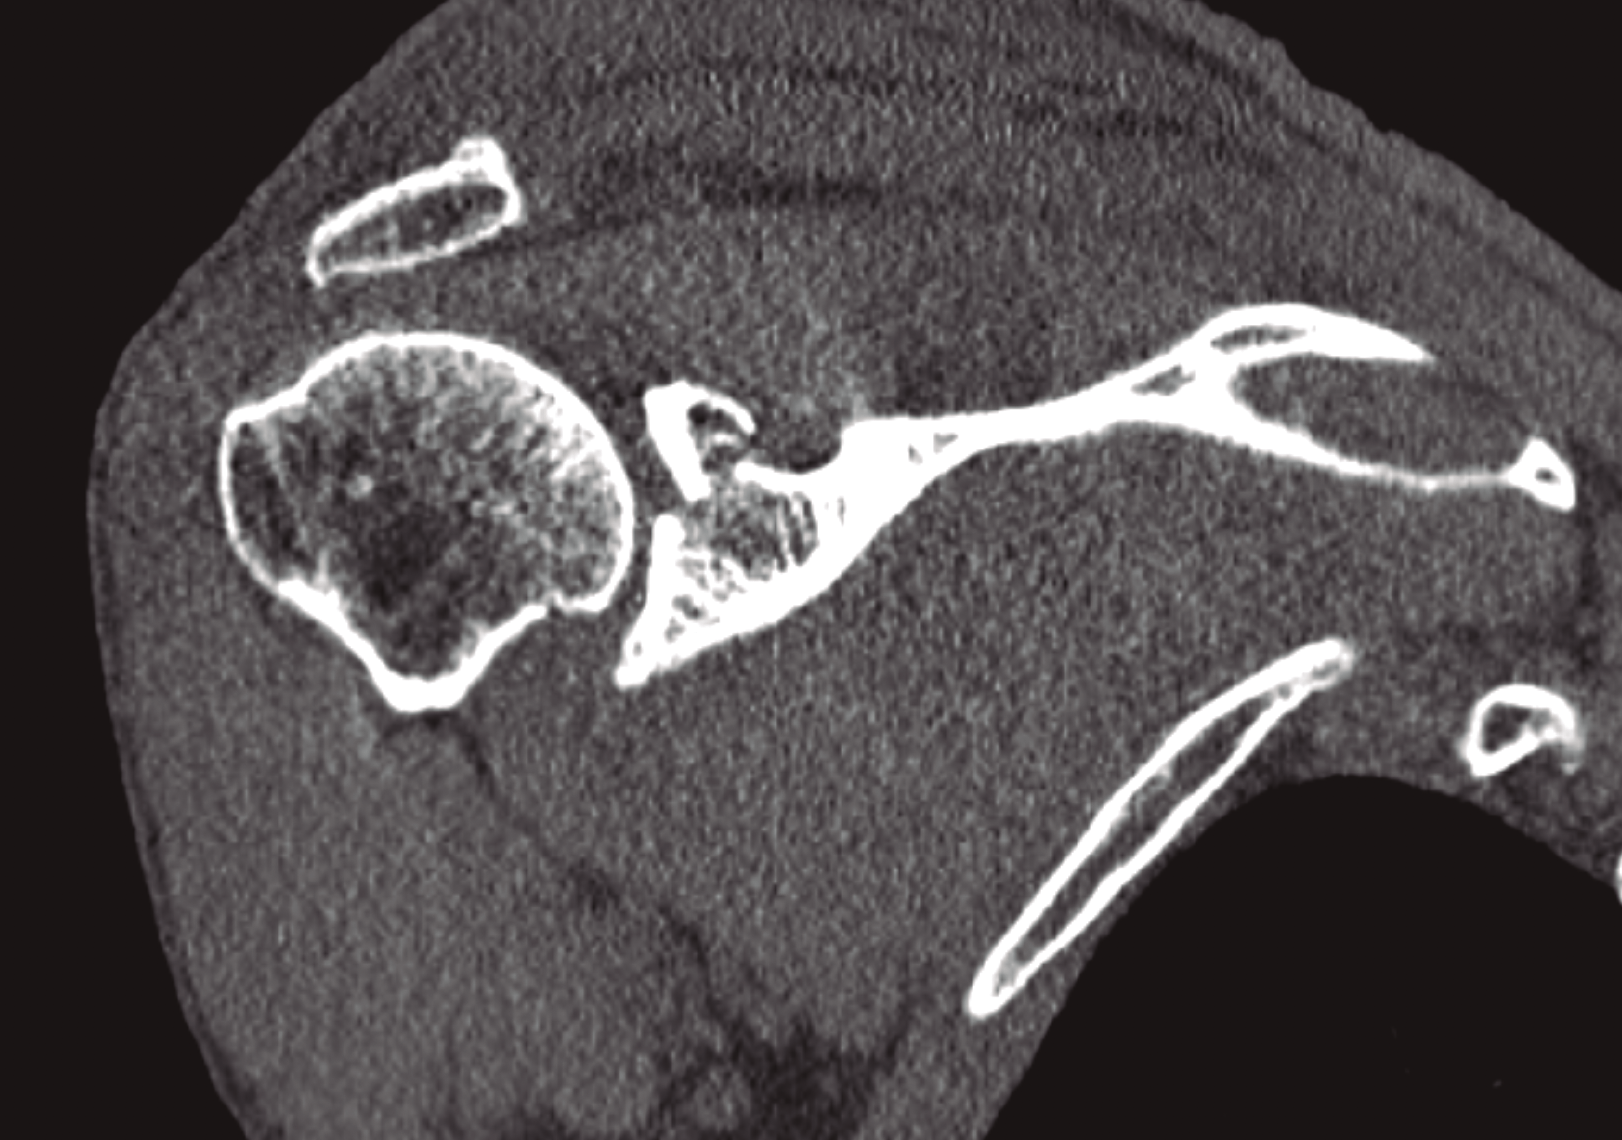

El complejo suspensorio superior del hombro es un anillo óseo y de tejidos blandos formado por el rodete glenoideo, la coracoides, el ligamento coracoclavicular, la porción distal de la clavícula, la articulación acromioclavicular, el ligamento coracoacromial y el acromion. La lesión de dicho anillo a 2 niveles supone una alteración biomecánica importante, que requiere tratamiento quirúrgico dado el potencial de inestabilidad que supone la disrupción del complejo suspensorio del hombro. Presentamos el caso de un paciente que sufrió fractura del acromion y de la cavidad glenoidea con desplazamiento significativo. Tras la estabilización del paciente se procedió a la osteosíntesis de la glena y el acromion con tornillos mediante un abordaje deltopectoral.

The superior shoulder suspensory complex is a bone and soft tissue ring formed by the glenoid cavity, the coracoid, the coracoclavicular ligament, the distal portion of the clavicle, the acromioclavicular joint, the coracoacromial ligament and acromion. The lesion of the ring at 2 levels implies an important biomechanical alteration, which requires surgical treatment because of the potential for instability that involves the disruption of the superior shoulder suspensory complex. We present the case of a patient who suffered a fracture of acromion and glenoid cavity with significant displacement. After stabilization of the patient, osteosynthesis of the glena and acromion with screws was performed using a deltopectoral approach.